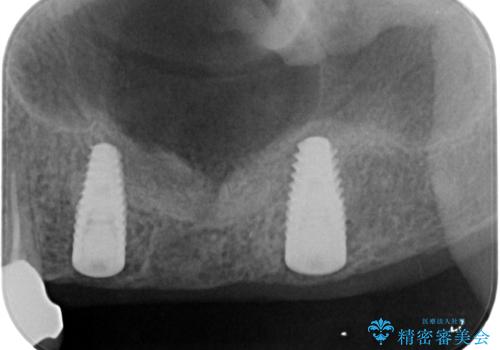

3本の歯(クラウン)を2本のインプラントで支えるインプラントブリッジによる咬合機能の回復を計画します。

また十分な骨の厚みを確保するためソケットリフト法を併用し、長期的な安定を見込めるインプラント治療を実践します。